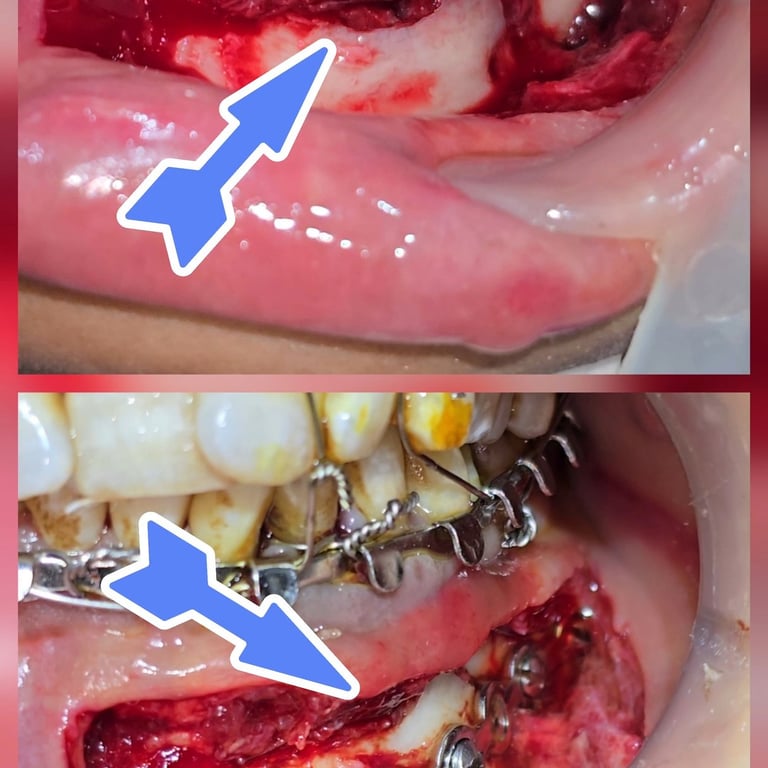

Facial trauma cases involving mandibular fractures are among the most common maxillofacial emergencies seen in dental and surgical practice. A fractured jaw not only causes severe pain and swelling but also affects chewing, speech, and overall facial aesthetics. In this blog, we present a rare case of multiple mandibular fractures in a 40-year-old female patient, including angle fracture, parasymphysis fracture, condylar fracture, and coronoid fracture—all treated successfully with intermaxillary fixation (IMF) and plating.